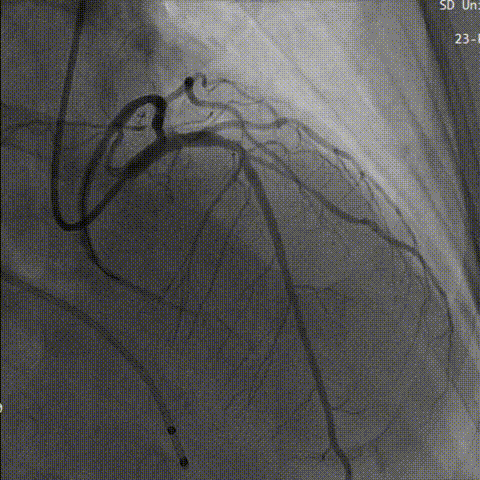

术前先行冠脉造影,回旋支中段狭窄,右冠未见明显异常。

左冠造影

右冠造影

左冠回旋支行PCI治疗,造影显示回旋支充盈良好。

左冠PCI治疗

造影评估